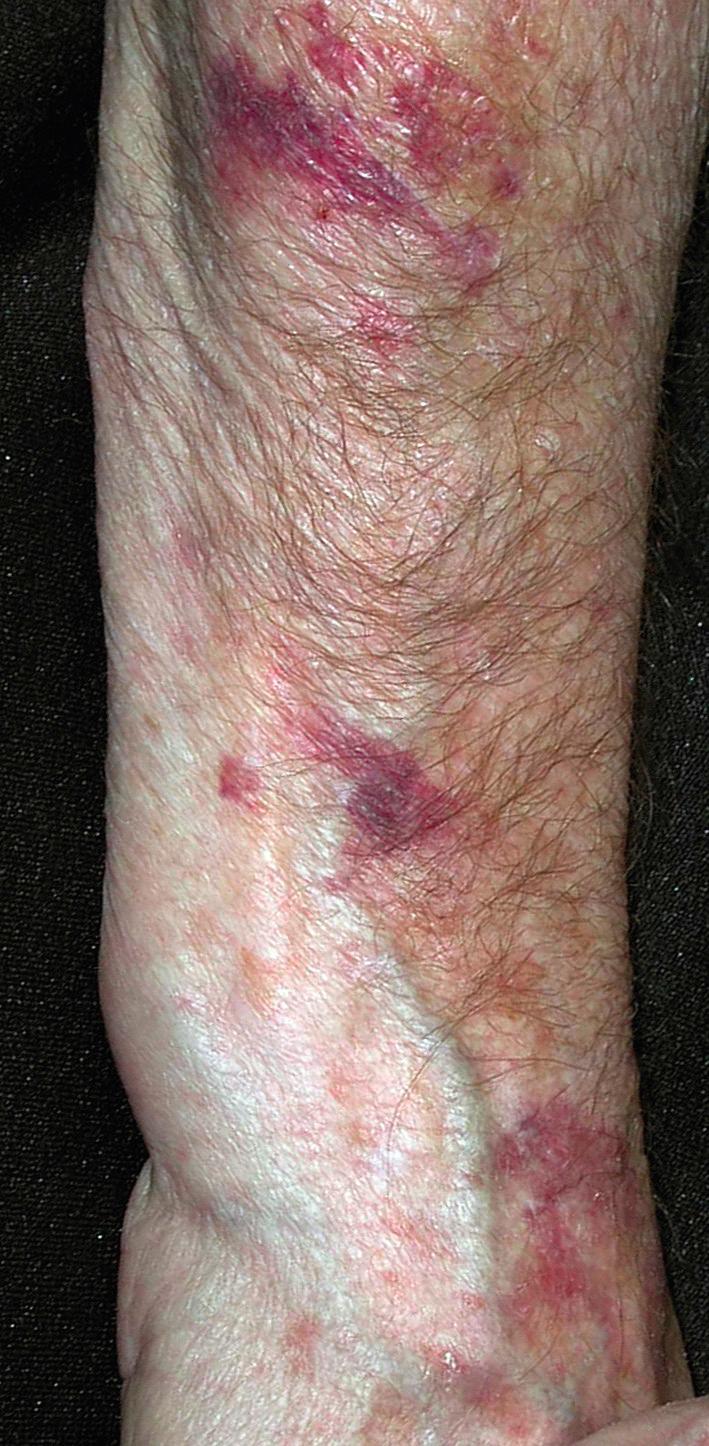

Fig. 15.2, Cutaneous blood vessels are easily damaged by trivial external trauma to sun-damaged skin resulting in asymptomatic but unsightly ecchymosis. Aspirin therapy worsens solar purpura. Regular use of sunscreen and alpha-hydroxy acid moisturizer are of some benefit.

Fig. 15.7, Sun-damaged skin. Bleeding occurs with the slightest trauma to the sun-damaged surfaces of the forearms and hands. The fragile skin tears easily and heals with crisscrossed scars.